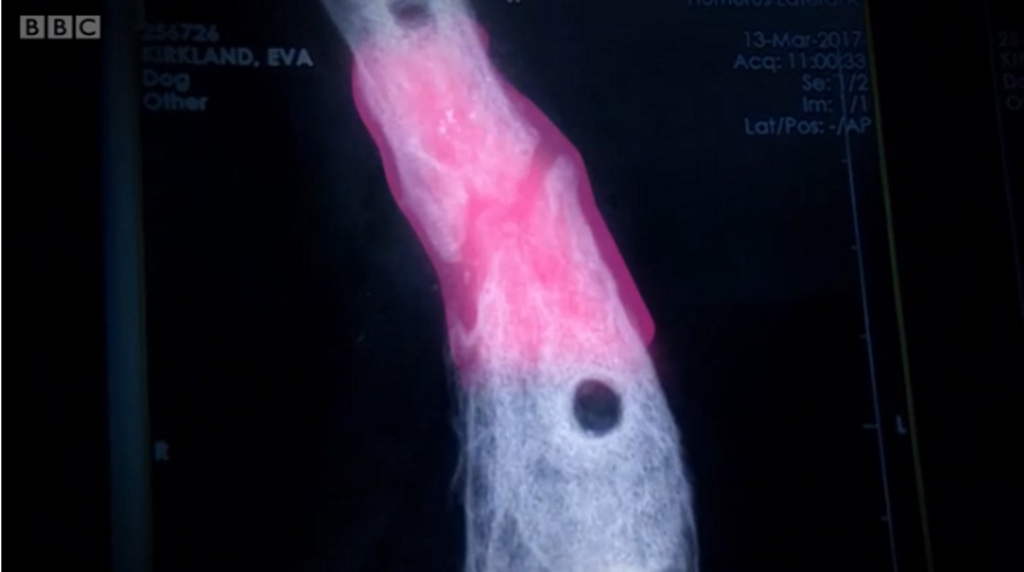

Собака не міг ходити, того як його збила машина і він отримав перелом ноги. Травма була настільки серйозна, що довелося відрізати кінцівку. Проте її врятували науковці, у лабораторії вони виростили з частини кістки – нову.Науковці вкрили частину кістки пластмасою та хімічними речовинами – через 6 тижнів кістка була повністю зцілена. Це перше таке лікування в світі, передає ВВС Україна.